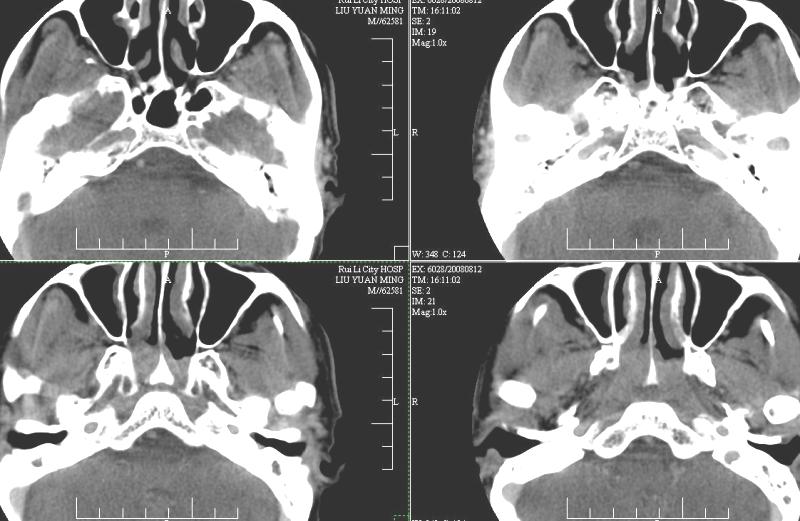

以下是引用ydx_74在2008-8-12 22:09:00的发言:[br]不考虑鼻咽癌。没有淋巴结肿大,没有颅底骨质破坏,咽隐窝、咽鼓管咽口存在,咽旁间隙清楚,平扫ct值34hu,增强动脉期81hu,实质期约85hu,增强幅度达50多,除外增强时机没有掌握好因素,可以考虑鼻咽纤维血管瘤吗?

以下是引用卜一在2008-8-13 8:07:00的发言:[br][br] 鼻咽部新生物,性质待定(不排除鼻咽癌可能);建议行鼻咽镜检查(活检)。 [br]支持!

以下是引用xulianj在2008-8-12 21:30:00的发言:[br]建议活检!结节病?咽淋巴结炎?肿瘤待排。